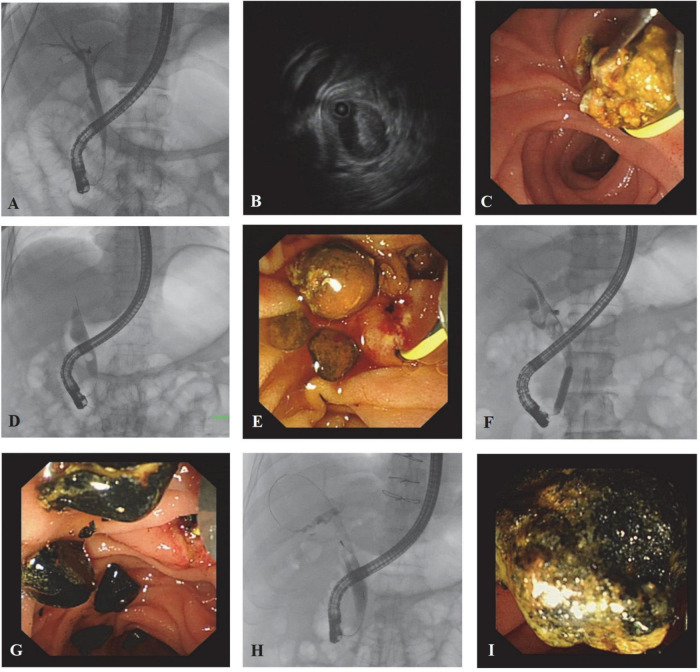

Before stones removal, there were a few patients in the three groups whose stones were not accurately evaluated. Both the size and the amount of the stones predicted in advance deviated from the final diagnosis. The accuracy of stone size prediction in the IDUS-BL, IDUS-ALC, and IDUS-AL groups was 86.9% (53/61), 85.5% (53/62), and 88.5% (54/61), respectively, while the accuracy of judging the number of stones in the three groups was 95.1% (58/61), 87.1% (54/62), and 83.6% (51/61), respectively. There was no significant difference among the three groups in the overestimation or underestimation of the size or amount of stones (all P > 0.05). Repeated lithotomies were done in 5, 9, and 9 cases of IDUS-BL, IDUS-ALC, and IDUS-AL group, respectively. No statistical difference was found in the frequency of RL and finding of RL (> or <3 mm calculus) among the three groups (Table 3 and Figures 2, 3)

Generally speaking, no residual stones were found during follow-up in the three groups, and no serious complications occurred. Compared with other researches, we achieved a lower complication rate, which can be partly attributed to the assistance of general anesthesia and proper indication for ERCP. The shorter average FT can be due to the personal experience of the operator. Moreover, RL during ERCP was not emphasized by other researchers. Our study showed that RL was related to the accuracy of stone prejudgment. Inaccurate prejudgment led to a higher RL rate. Also, both lithotripsy and bile duct diameter were relevant to RL. After lithotripsy, many stone fragments were produced, so it is difficult to judge whether all the stones were removed. Previous studies have suggested that biliary stenting after lithotripsy is safe, which is consistent with our experience (ref. 20). When the bile duct is too wide, it can lead to inadequate angiography, making the basket empty out and the balloon not fit the bile duct wall. The high sensitivity of IDUS makes it possible to detect stones 1–2 mm in size. We are also concerned about whether the stones removed in RL are larger than 3 mm, because stones larger than 3 mm might cannot be automatically discharged. The high sensitivity of IDUS may also lead to misjudgment. Thick bile, guidewire, blood clot, and bubbles need to be differentiated from stones (Figure 3).